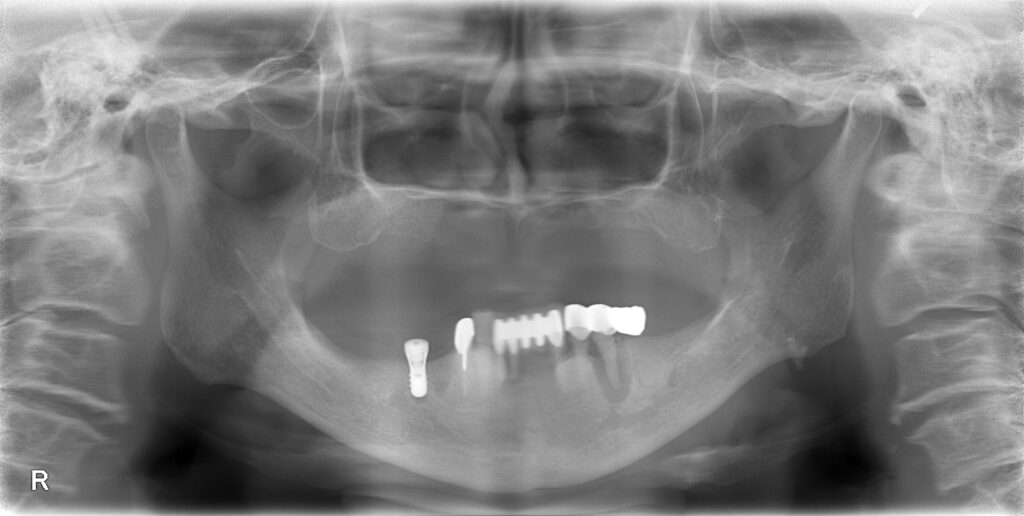

さて、現在はインプラントを埋入し、割れた右下の歯を抜歯しました。

それが以下のレントゲンです。

【インプラント埋入直後のレントゲン写真】

CTを撮影し、安全に処置行っております。

処置時間は30分程度です。